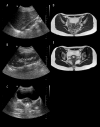

A 13-year-old girl with pelvic pain and bad-smelling, green-coloured vaginal discharge, case I. On axial sonography at the level of the vaginas, (A) more to the left side (star), both hemivaginas are dilated and have fluid echoes. Axial T2W images at the level of uterus (B) and vaginas (C) show uterus didelphis and dilated right (arrow) and left (star) hemivaginas with slightly hypointense fluid contents consistent with haematocolpos. Note the tubular cystic structure in the wall of the left hemivagina (arrowhead).

Figure 2

A 15-year-old girl with dysmenorrhea, case II. On a sagittal view, the right kidney (A) was absent and the left kidney (B) was hypertrophic. Axial sonography image (C) demonstrates dilated left hemivagina with echogenic content (arrowhead) and normal right hemivagina (arrow). Axial T2W images at the level of uterus (D) and vaginas (E) show uterus didelphis and dilated left hemivagina with slightly hypointense fluid consistent with haematocolpos (star) and normal right hemivagina (arrow).